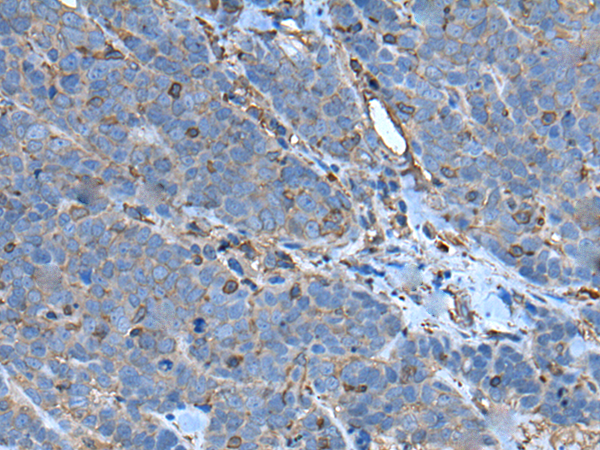

分类: 科研抗体货号: P05257别名: SCP2; SCP-2应用: IHC反应种属: Human, Mouse, Rat